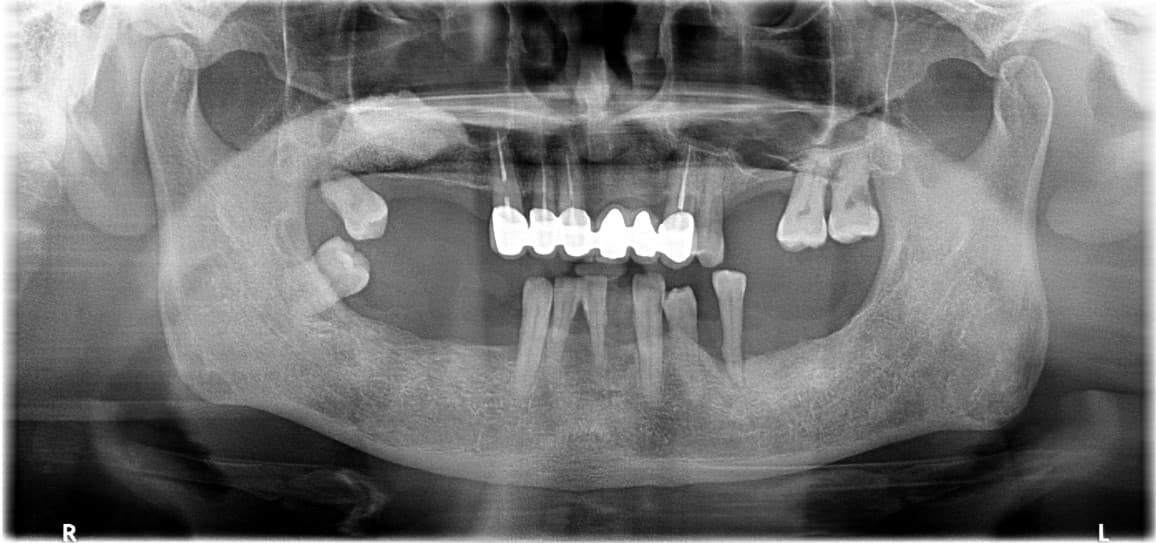

Phục hồi toàn hàm

Những trường hợp sức khỏe răng miệng bị hủy hoại hoàn toàn

được phục hồi trở lại cuộc sống bình thường

Điều trị tổng thể bởi bác sĩ chuyên khoa Phục hình

Bác sĩ phục hình của chúng tôi kết hợp tối ưu các phương pháp điều trị bao gồm Implant, răng sứ và cầu răng để tạo ra kết quả tốt nhất với chi phí hợp lý.

Phục hồi toàn hàm · Ông S●● · Nam, 70 tuổi